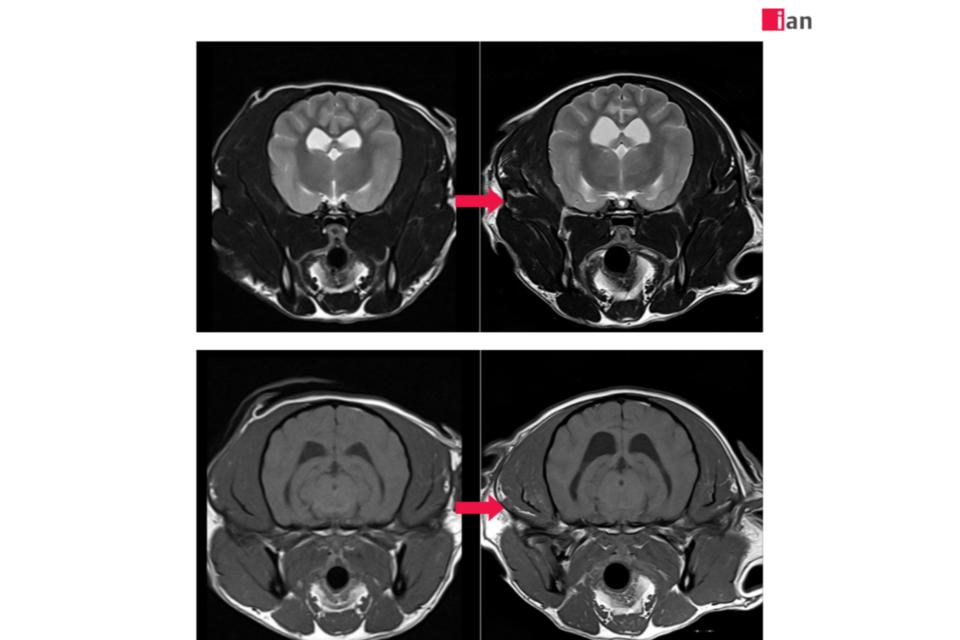

2023년 말 최첨단 AI MRI 소프트웨어를 도입한 이안동물의학센터는 촬영 시간 단축과 영상 품질 극대화라는 두 마리 토끼를 동시에 잡았다. 딥러닝 알고리즘을 통한 이미지 재구성과 노이즈 제거, 선명도 향상은 보다 신속하고 정확한 진단을 가능하게 했으며, 보호자와 반려동물 모두에게 높은 만족도를 제공하고 있다.

특히 AI 소프트웨어 도입 이후 촬영 시간이 기존 대비 최대 절반으로 줄어드는 등 검사 효율성이 크게 향상됐다. 이는 보호자들의 시간적 부담을 덜어줄 뿐 아니라 환자의 마취 시간 단축으로 검사 안전성을 더욱 높이는 효과를 가져왔다.

또한 이미지 퀄리티 향상으로 정밀한 판독이 가능해져 질병의 조기 발견과 정확한 진단을 통한 치료 전략 수립에 커다란 진전을 이뤄냈다. 여기에 이안동물의학센터 전담 마취팀의 철저한 관리까지 더해져 반려동물 검사 전 과정에서 신뢰도 높은 의료 서비스를 제공하고 있다.